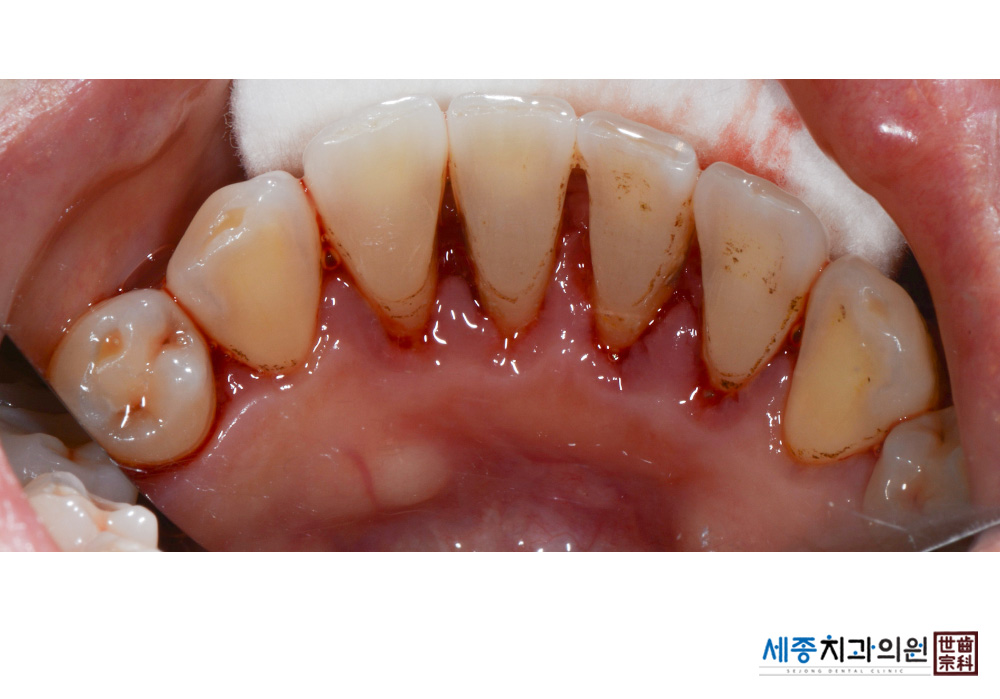

[스케일링] 치주질환 예방 스케일링 치료

치료후 : 2019-03-13

가글마취&저주파 스켈러를 사용한 스케일링